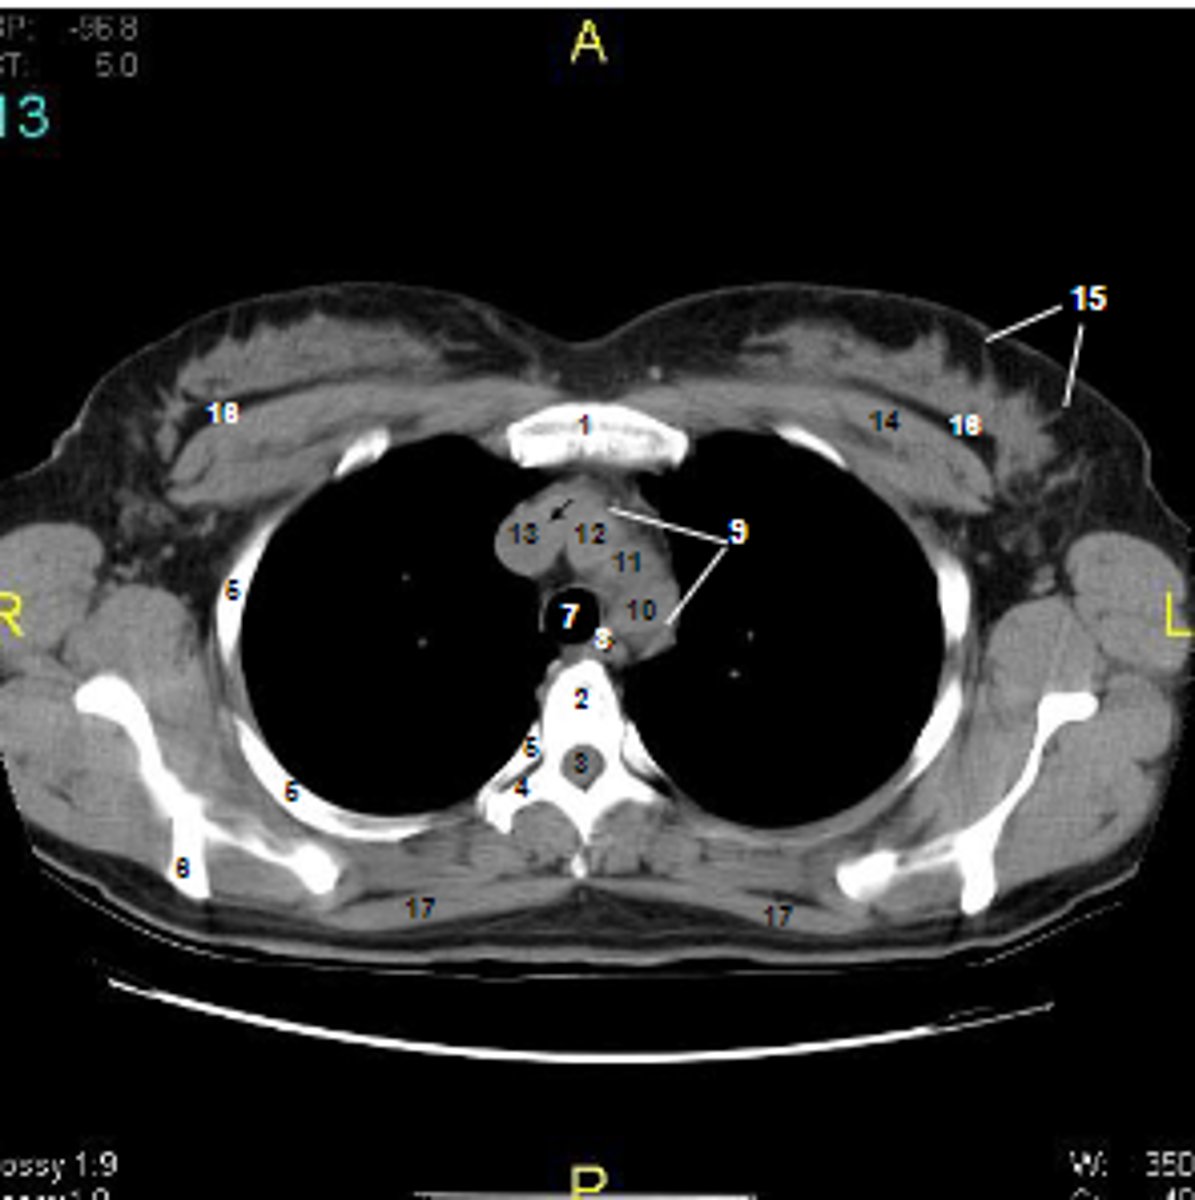

1

at what number is the sternum

2

at what number is the vertebral body

3

at what number is the vertebral canal/ spinal cord

4

at what number is the transverse process of vertebra

5

at what number is the rib

6

at what number is the spine of scapula

7

at what number is the trachea

8

at what number is the esophagus

9

at what number is the arch of aorta

10

at what number is the left subclavian artery

11

at what number is the common carotid artery

12

at what number is the brachiocephalic trunk

13

at what number is the superior vena cava

14

at what number is pectoralis major

15

at what number are Cooper's ligaments

16

at what number is the retromammary space

17

at what number is trapezius